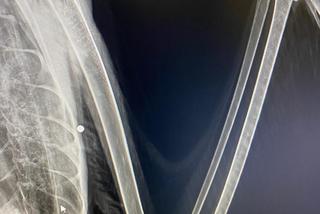

Łabędzica Lusia nie lata już bardzo długo, a świadczą o tym pióra w ogonie, które zmieniły kolor. Ptak bardzo cierpi. W swoim ciele ma śruty, które uszkodził mu skrzydło oraz dziób. Ktoś bezmyślnie strzelał do tego zwierzęcia.

Lusia trafiła do Fundacji Ada w Przemyślu, gdzie weterynarze natychmiast udzielili jej pomocy i od razu zdiagnozowali problem. Do ptaka ktoś strzelał z wiatrówki. Zadał łabędzicy  ból i skazał ją na cierpienie dla zabawy! Zwierzę ma uszkodzony dziób i staw w skrzydle, przez co nie może latać, a kości bez pomocy weterynarzy nie zrosną się. Lusia zostanie w Lecznicy póki nie wyzdrowieje.